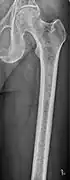

The diagnostic examination of a person with suspected multiple myeloma typically includes a skeletal survey. This is a series of X-rays of the skull, axial skeleton, and proximal long bones. Myeloma activity sometimes appears as "lytic lesions" (with local disappearance of normal bone due to resorption). And on the skull X-ray as "punched-out lesions" (pepper-pot skull). Lesions may also be sclerotic, which is seen as radiodense.[48] Overall, the radiodensity of myeloma is between −30 and 120 Hounsfield units (HU).[49] Magnetic resonance imaging is more sensitive than simple X-rays in the detection of lytic lesions, and may supersede a skeletal survey, especially when vertebral disease is suspected. Occasionally, a CT scan is performed to measure the size of soft-tissue plasmacytomas. Bone scans are typically not of any additional value in the workup of people with myeloma (no new bone formation; lytic lesions not well visualized on bone scan).

-

Femur with multiple myeloma lesions -

Same femur before myeloma lesions for comparison -